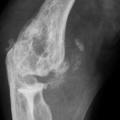

Les radiographies permettent de déceler des modifications ostéocartilagineuses asymétriques (mains, pieds, poignets, coudes, genoux), secondaires à la réaction inflammatoire autour des tophus, comportant :

• des érosions osseuses initiales caractéristiques : encoche épiphysaire (fig. 3) avec un éperon osseux (aspect en hallebarde) ;

• une image d’empreinte dans les parties molles (augmentation de la densité des parties molles dues au tophus) très évocatrice (fig. 4) ;

• un interligne longtemps conservé (contrairement aux autres rhumatismes destructeurs) [fig. 3] jusqu’au stade de goutte chronique et l’absence de raréfaction osseuse périarticulaire permettant de différencier la goutte d’autres arthropathies ; à un stade avancé, la goutte tophacée peut avoir un potentiel destructeur à la fois articulaire et osseux (fig. 4).